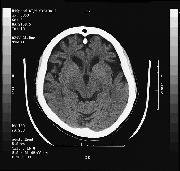

MRI showed a soft tissue lesion in the fourth ventricle (Fig. 1). This was consistent with a probable subependymoma which was thought to be an incidental finding. There was evidence of frontal lobe atrophy (Fig. 2).

figure 2

Figure 2. MRI T-1 study showing predominantly frontal lobe atrophy.

The findings are suggestive of a degenerative disease of the frontal lobes. The presence of impaired judgment and executive skills with normal visual spatial and mnemonic function seem to suggest this condition. These "frontal lobe" dementias histologically have been proven to be consistent with Pick's disease, subcortical gliosis, or simple neuronal loss. The history of normal cognitive performance in the face of poor judgment, poor executive function, and the imaging consistent with frontal lobe involvement are the basis of this diagnosis.